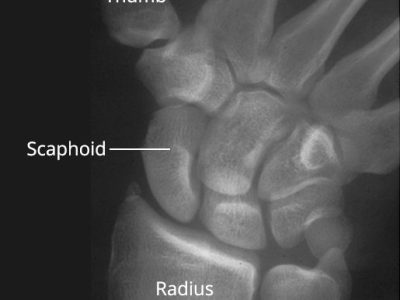

- Hand and wrist

Rephrased Paragraph: A wrist sprain happens when the resilient ligaments supporting the wrist are overstretched or torn. This typically results from a forceful bend or twist, often caused by falling onto an outstretched hand. Wrist sprains are frequent injuries that…